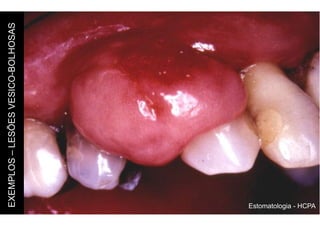

EXEMPLOS

–

LESÕES

VESICO-BOLHOSAS

Estomatologia - HCPA

Pequena elevação da mucosa (2 a 5mm) que

contém líquido em seu interior. Pode ser uma

lesão única ou múltipla.

Lesão de maior tamanho (mais do que 5mm).

Pode ser superficial ou profunda.